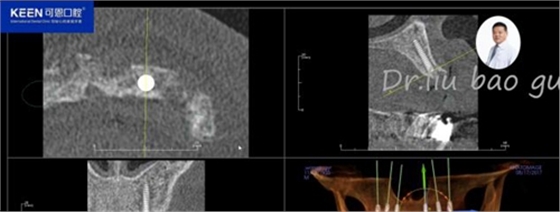

手術(shù)前種植軟件設(shè)計(jì)方案